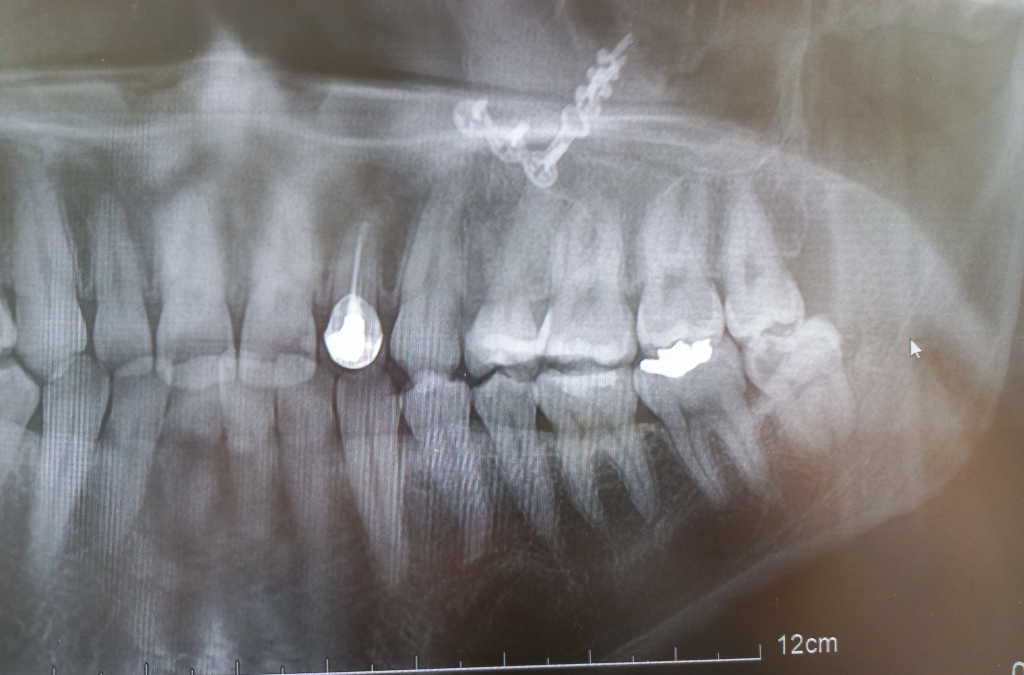

A치과에서는 사이충치 1곳 치료필요하고 사랑니 우측 하단 사랑니 1개 빼야한다고 했고 B치과 가봤더니 충치 8~9개 치료해야하고 사랑니도 4개 다 뽑아야한다고 하네요

사랑니는 치과의사마다 다를 수 있고 충치 갯수는 한곳으로 보이진 않고 다수가 보이고 있습니다.

우측 하단 사랑니는 무조건 뽑아야되는 사랑니인거 같고 나머지 사랑니도 관리가 안될꺼 같으니 뽑으라고 말한거 같습니다. 그리고 엑스레이상으로 인접면 충치가 다수보이긴 합니다.

3. 사랑니의 경우 파노라마 사진 상에서는 아래 2개는 일단 뽑는 것이 좋을 것 같습니다. 특히 아래 우측 사랑니는 옆 어금니에도 영향을 주고 있기 때문에 너무 늦지 않게 뽑는 것이 좋을 것 같습니다.